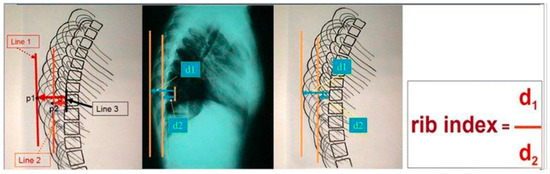

2. The Presented Sign and Index (DRCS and RI)

In Scoliosis Clinics at the Thriasio General Hospital of Greece, during the clinical assessment of asymmetric children referred for IS from the school scoliosis screening (SSS) program of the hospital with the Adams test, it was noticed by TBG that the contours of the two hemithoraces were always overlapping one over the other; in other words, they were shown to be asymmetrical in the lateral spinal radiographs. This observation was systematically noted, no matter if the spines of these children were found scoliotic or not in the prescribed radiographs. This overlap was coined the “double rib contour sign” (DRCS) [9], as shown in Figure 1. Consequently, the need for quantification of the degree of this overlap, which is the asymmetry of the DRCS—in other words, the thoracic deformity in the transverse plane—triggered the introduction of the RI [9], as shown in Figure 2. The use of the index prevents metric errors due to the varying magnifications of the films depicting the thorax. This novel sign and index were presented in Greece in 1999 and in France in 2000, and published in 2002 [9,10,11]. However, this publication [11] focused merely on the implications of the DRCS in the etiology of IS.

Figure 2.

The rib index (RI) of the thoracic cage in a standing spinal radiograph (from citation no. [12]).